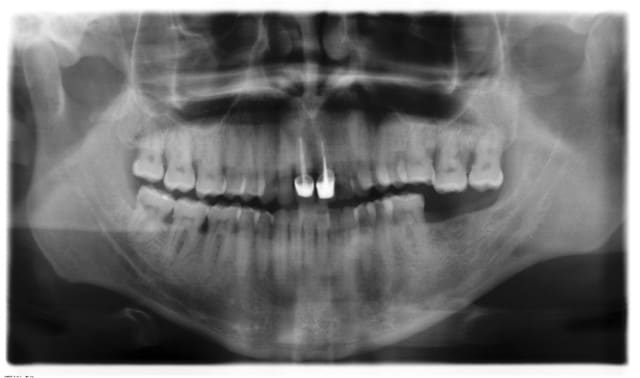

J'ai vu ce patient en consultation ce matin.

Je prevois :

-det haut et bas.

-soins caries 24mesial, 25-26 proximal, sillons sur 17.

-implant sect 3 pour remplacer 37

-ext 28

-Surfaçage sect 2+ crn 27 pour rétablir courbe de Spee pendant cicatrisation.

-11 et 21 seront refaites car gingivite localisée chronique due à surcontours sur les deux dents + esthétique à revoir.

- réalisation prothèse sur implant 37.

Voila en gros le plan des travaux. A vous, expéimentés, feriez-vous de meme?

Je ferais deux bite-wings,car là il faut etre magicien pour faire un plan de traitement.Ensuite,le surfaçage ne me semble pas objectivé par des poches de plus de 3 mm.Je me souviens d'une étude présentée par le prof de paro de la fac de Strasbourg qui considérait qu'un surfaçage précoce était iatrogène.Bon week-end.